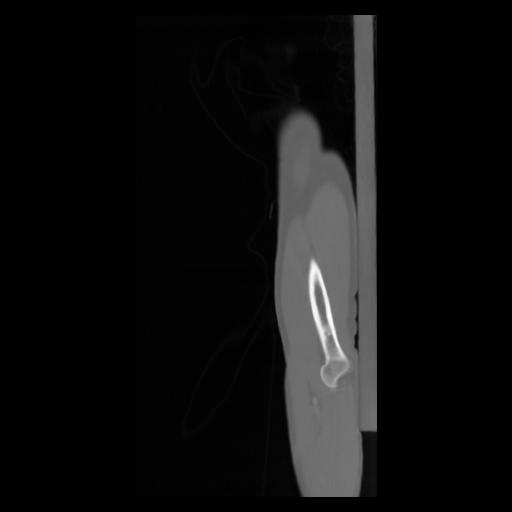

30 CUERPO,CE,Sagittal,3.000,CUERPO,Sagittal,